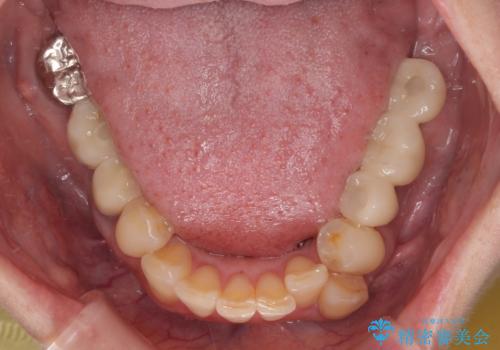

セラッミクインレー|オールセラミッククラウン|銀歯による二次カリエス|ラバーダムシート使用

銀歯の下の虫歯|オールセラミッククラウン|歯を長持ちさせるための治療|歯の神経を守る